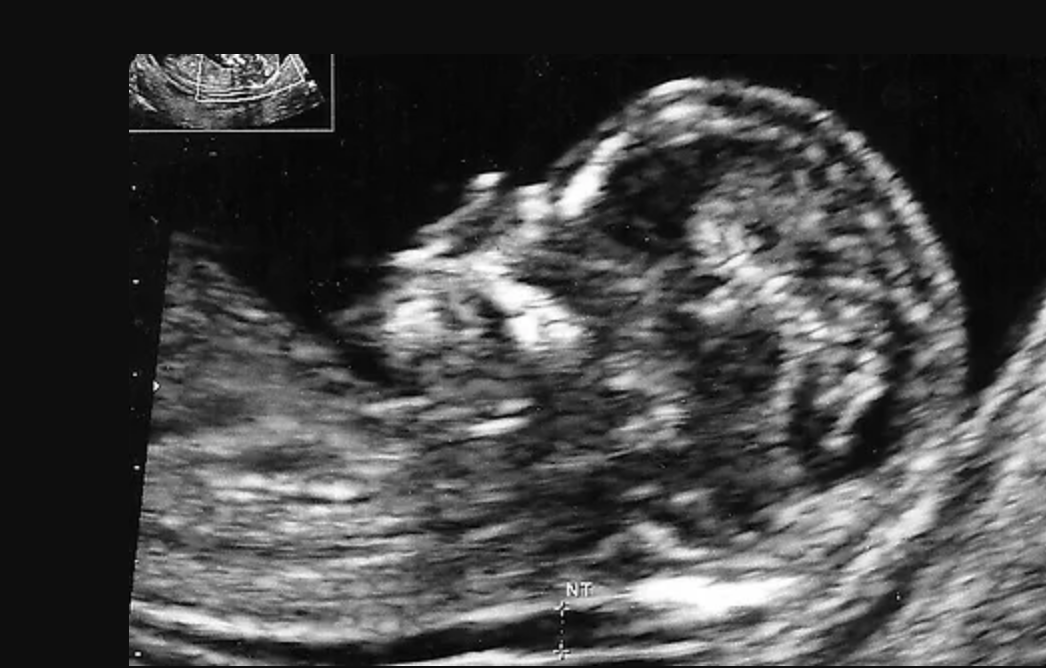

Nakkefoldsscanning,

Hvornår ?

Nakkefoldsscanning er en vigtig del af graviditetens første trimester og bruges til at vurdere risikoen for kromosomafvigelser hos fosteret, såsom downs syndrom.

Nakkefoldsscanning foretages normalt i uge 11+4 - 13+6 af graviditeten. Ved hjælp af ultralyd måles tykkelsen af fosterets nakkefold, som kan give indikationer på eventuelle genetiske afvigelser.

Under en nakkefoldsscanning undersøger en specialist også andre fysiske egenskaber og markører, der kan pege på sundhedsmæssige problemer. Nakkefoldsscanningen er en sikker og smertefri procedure, der giver vigtige oplysninger om fosterets udvikling.

Mange kommende forældre vælger at få foretaget en nakkefoldsscanning for at få tidlig indsigt i deres barns sundhed. Resultaterne af en nakkefoldsscanning kan hjælpe med at planlægge yderligere tests eller forberede sig mentalt og praktisk på mulige udfordringer.

Det er vigtigt at bemærke, at en nakkefoldsscanning ikke giver en definitiv diagnose, men snarere en risikovurdering. Hvis scanningen viser en forhøjet risiko, kan yderligere tests anbefales for at få en mere præcis vurdering.  Nakkefoldsscanning er derfor et værdifuldt værktøj i moderne prænatal diagnostik, som hjælper forældre med at tage informerede beslutninger om deres graviditet.

At vælge at få en nakkefoldsscanning kan give ro i sindet og være et skridt mod at sikre det bedst mulige resultat for både mor og barn. Nakkefoldsscanninger er en integreret del af at sikre en sund graviditet.

Hvad er nakkefoldsscanning

Nakkefoldsscanning er en ultralydsundersøgelse omkring uge 11-14, der måler væsken bag babyens nakke. Den bruges til at vurdere risiko for kromosomfejl som Downs syndrom.